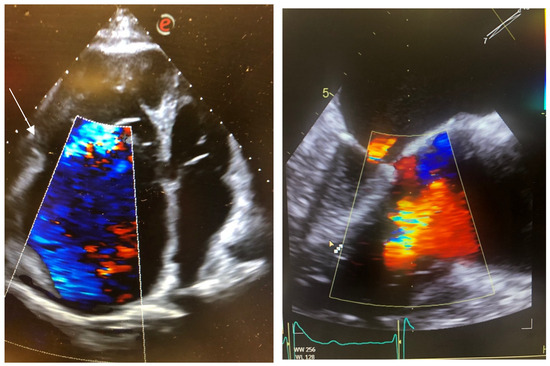

2. Case Reports

2.1. Case 1

2.2. Case 2

2.3. Case 3